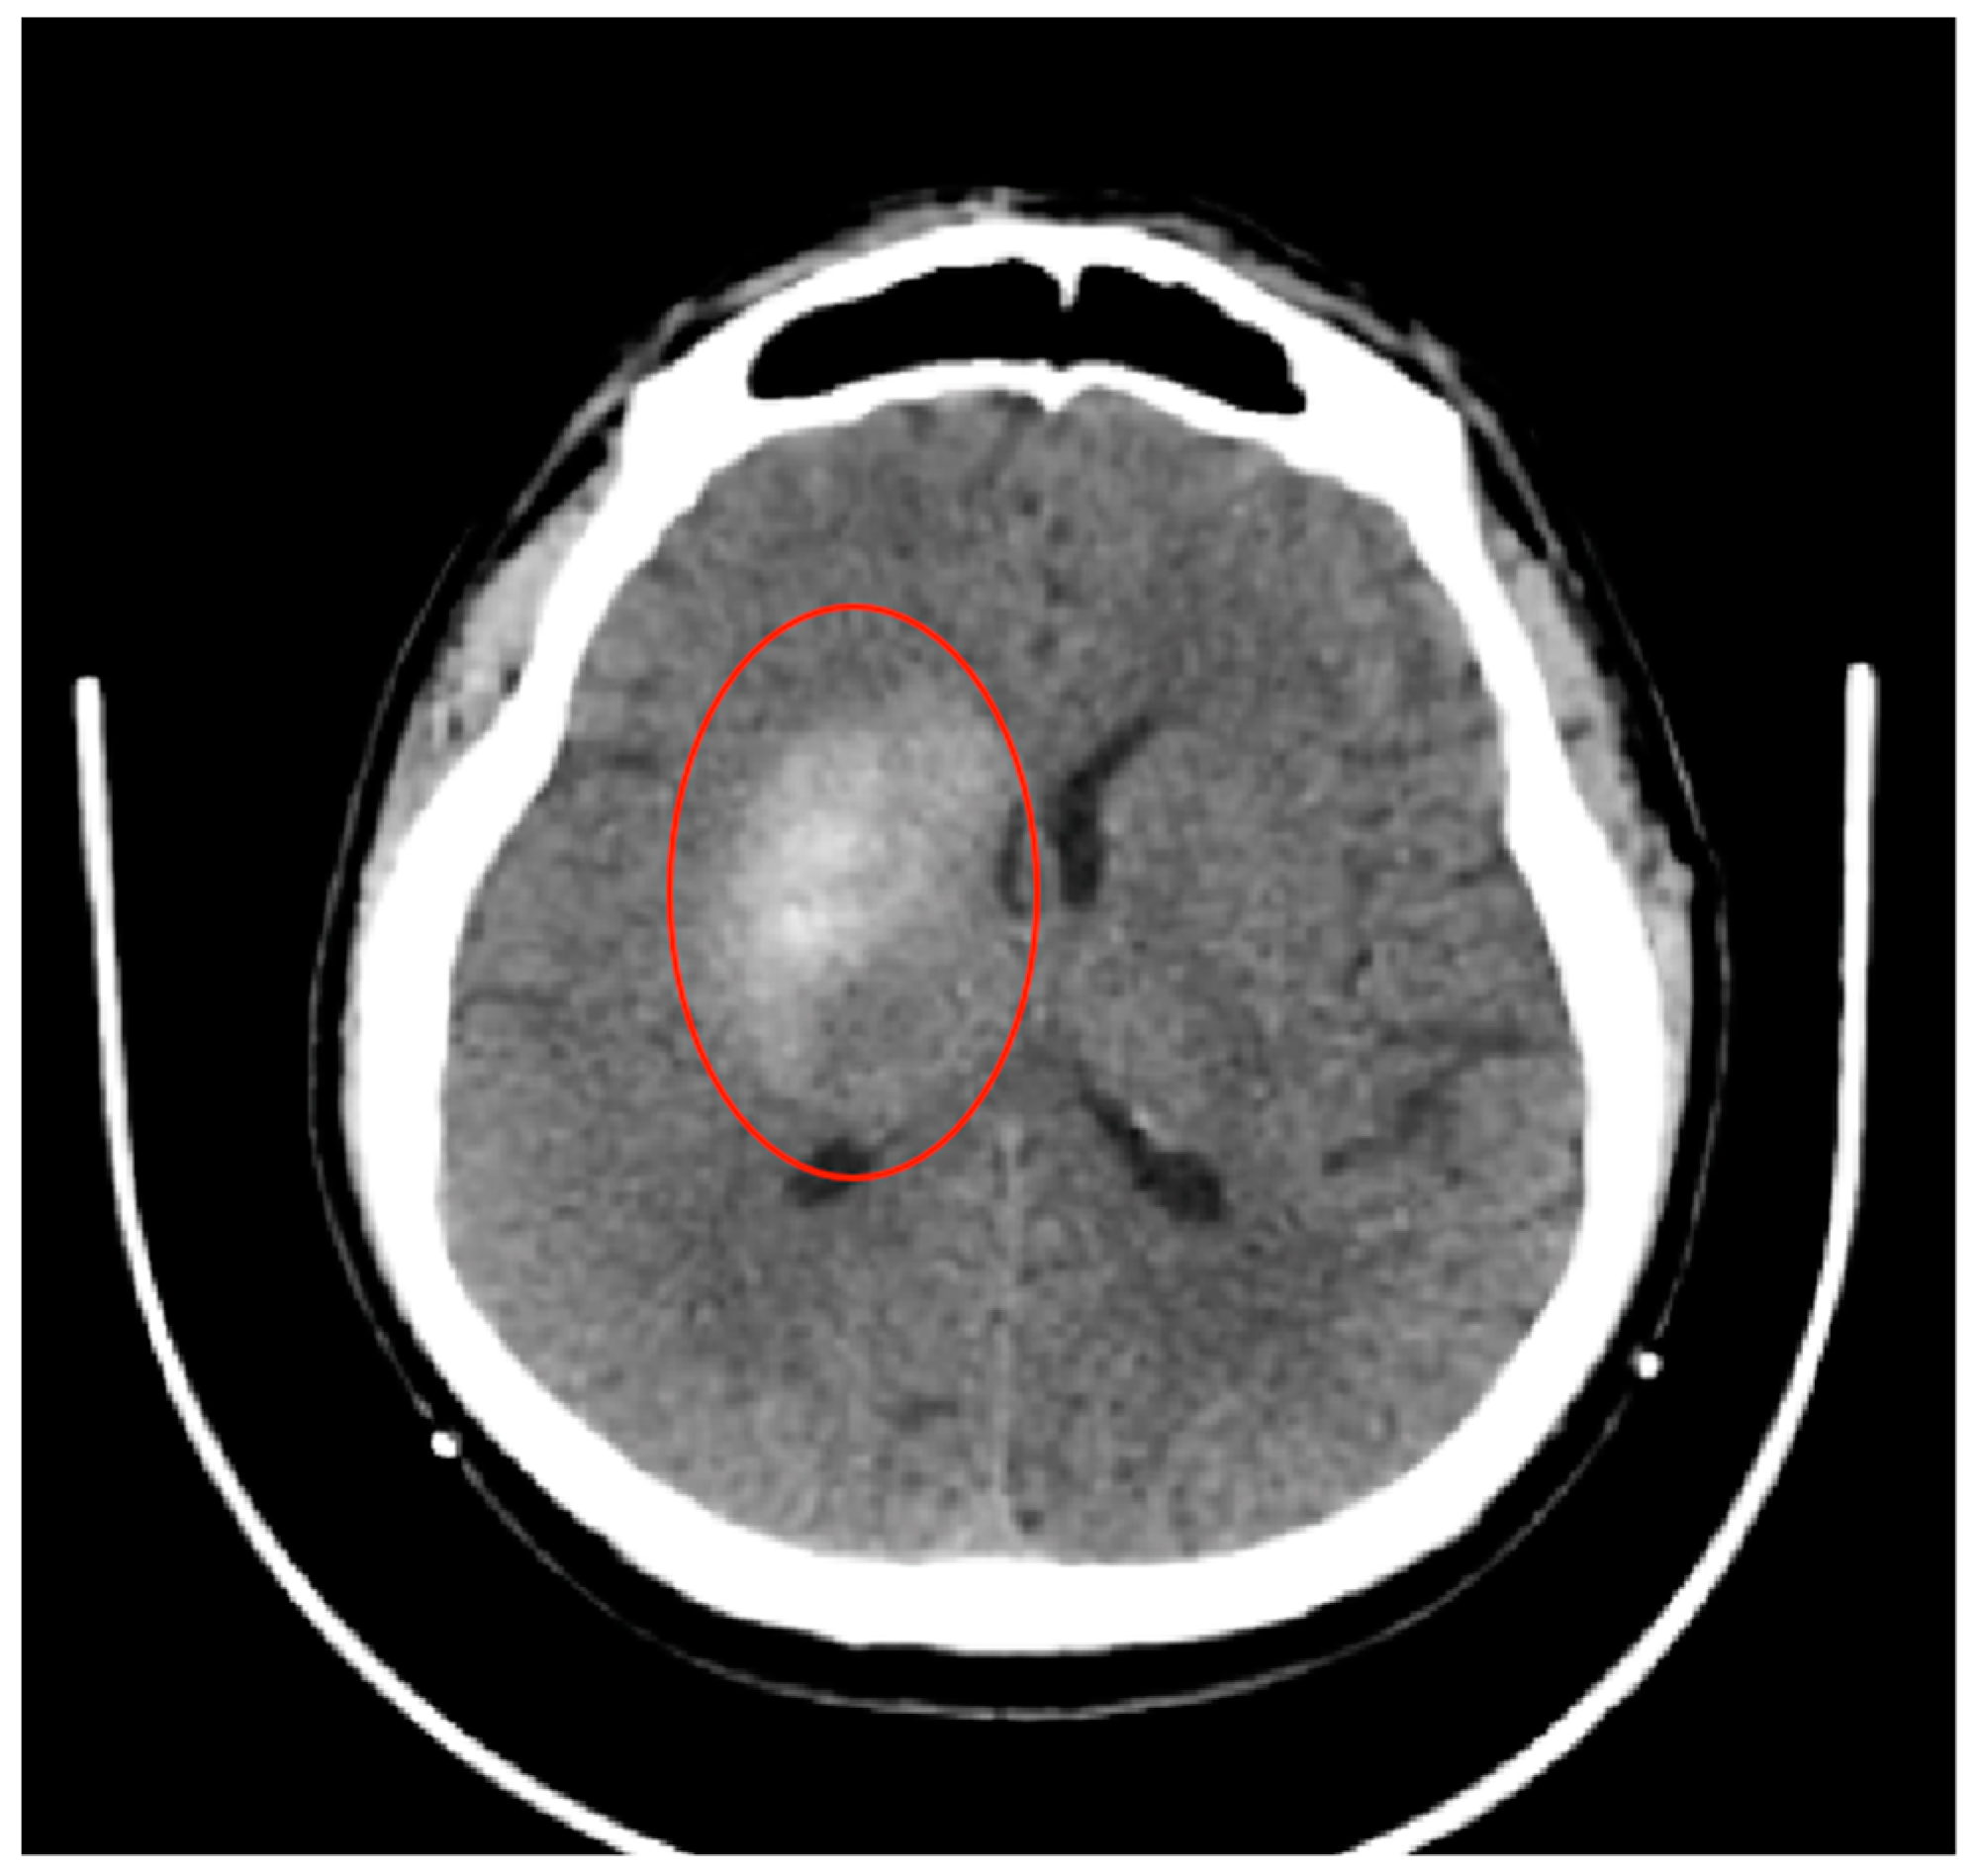

2.1. Case Presentation